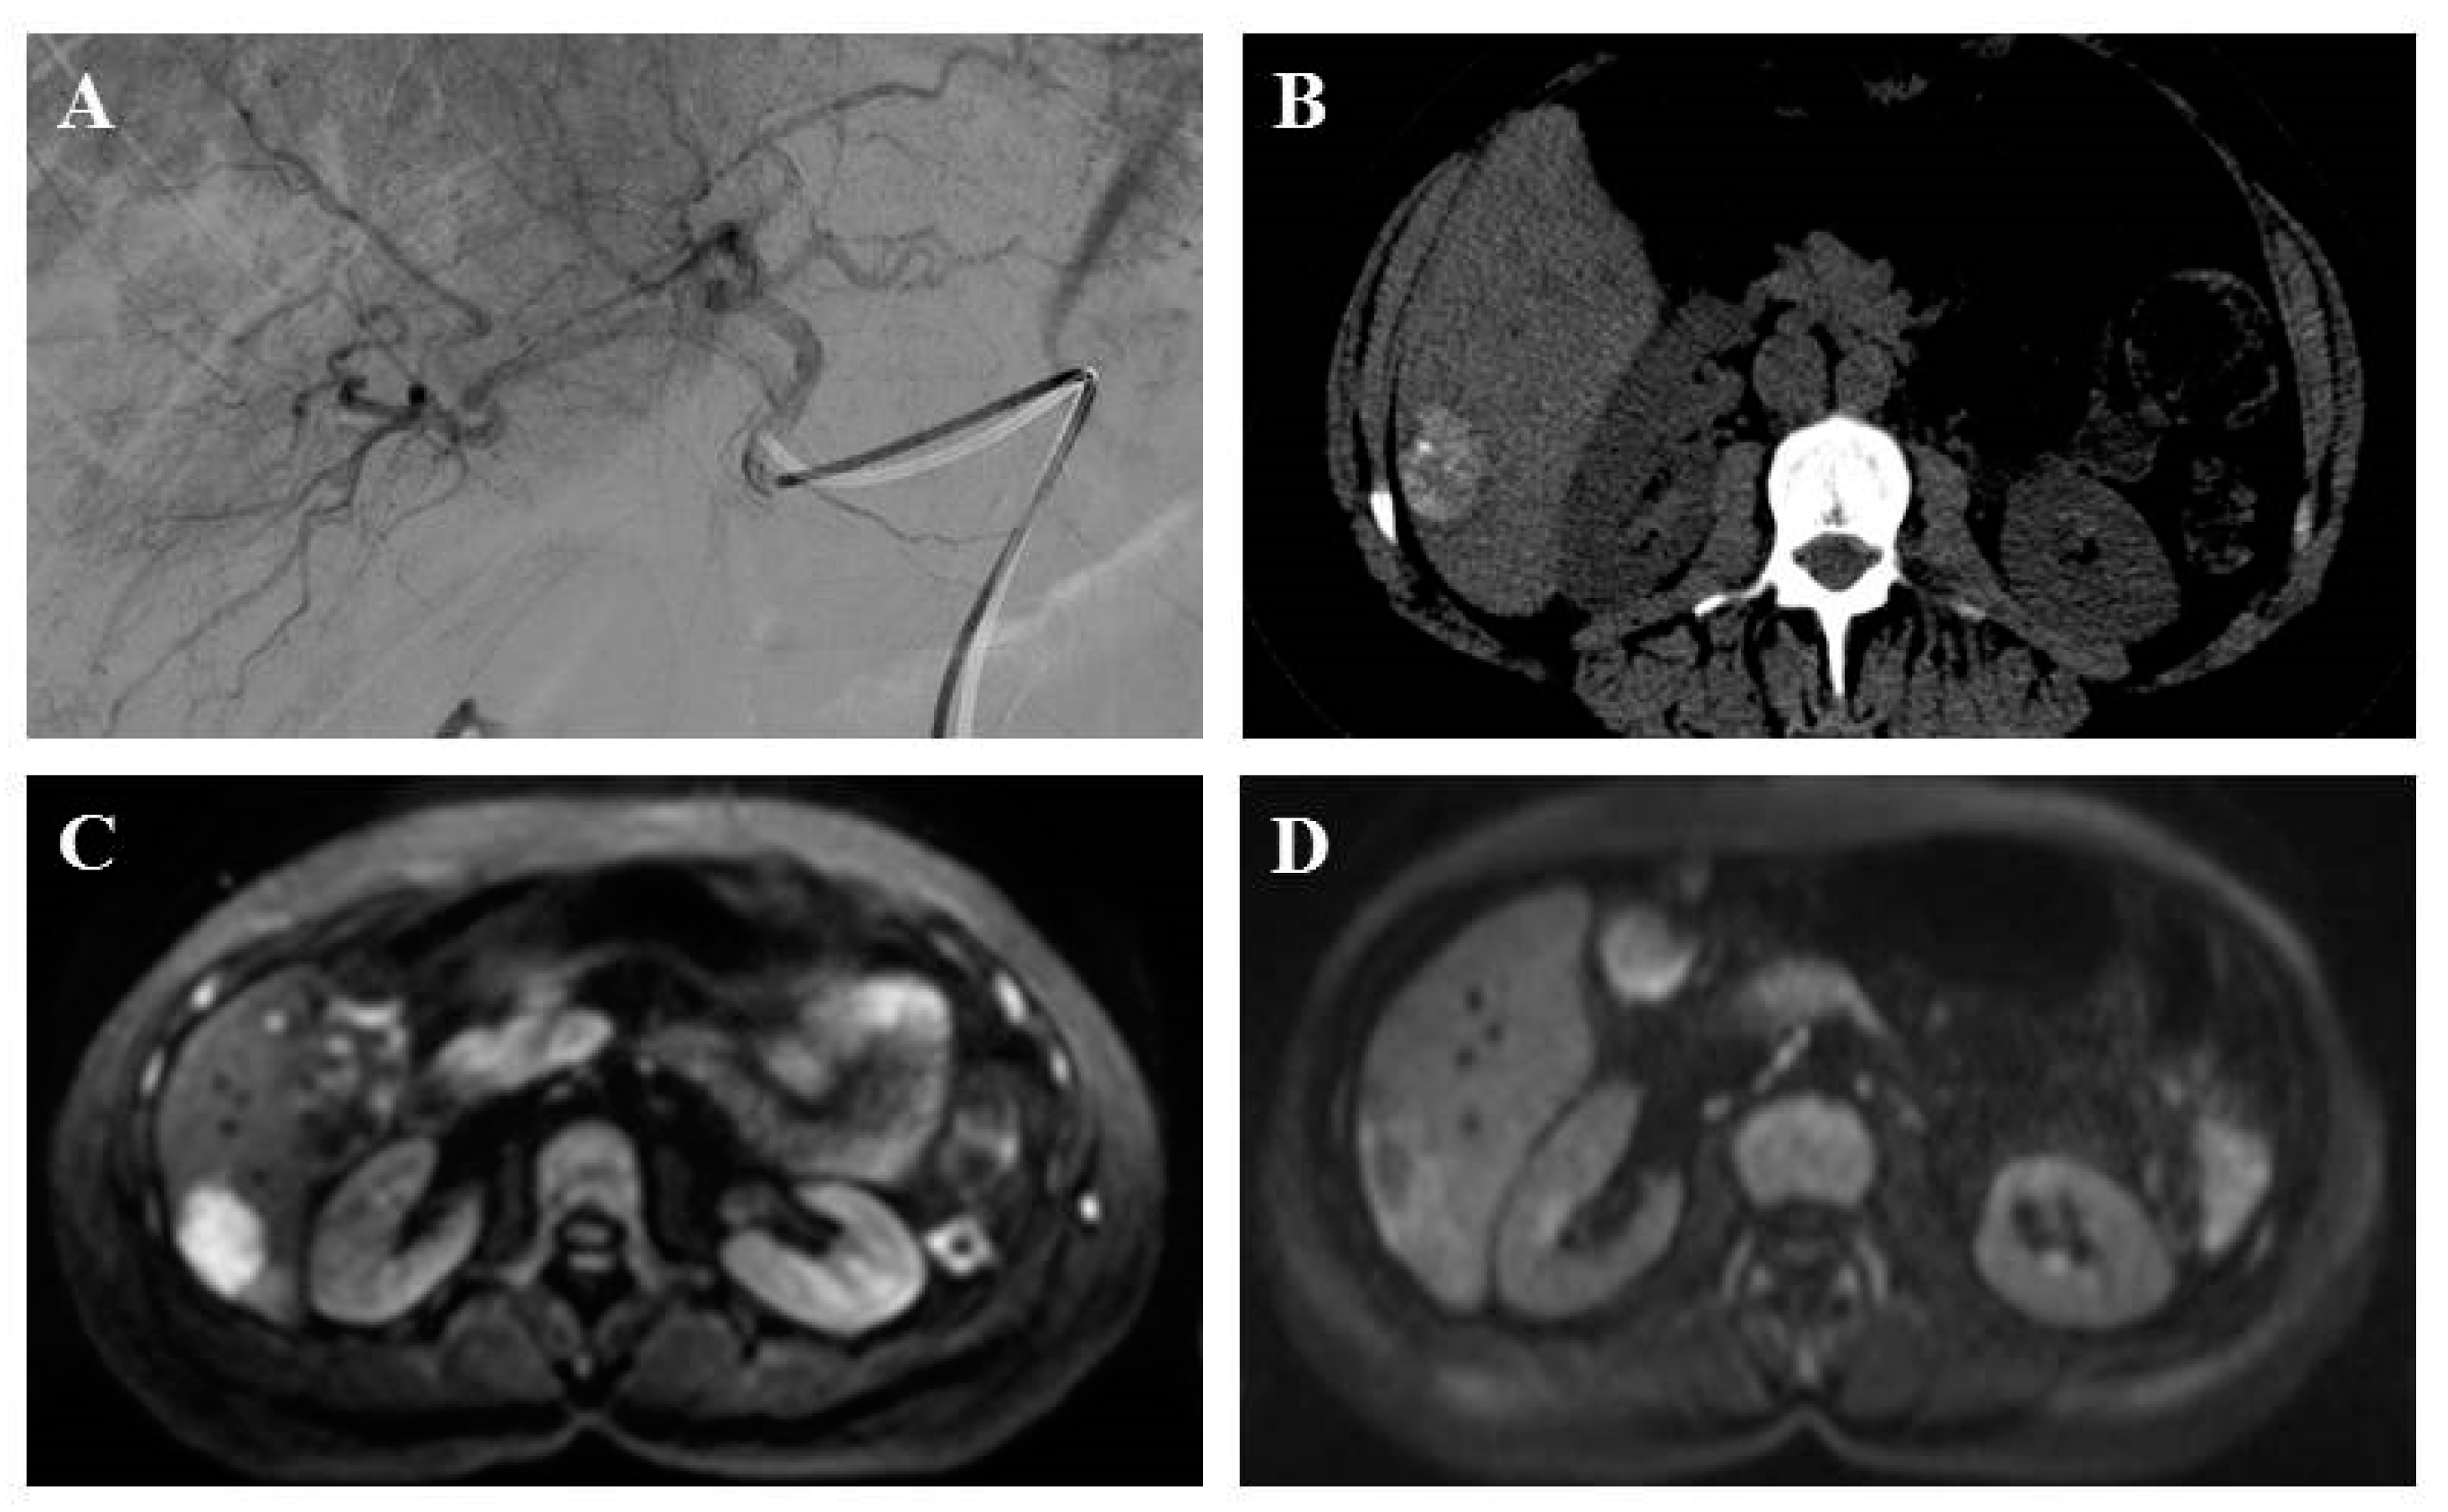

Figure 2.

A 51-year-old patient with liver metastasis from pancreatic grade 2 neuroendocrine tumor treated with lipiodol and doxorubicin chemoembolization. Prior to chemoembolization, the arteriography of tumor-feeding branches (2A) and diffusion-weighted axial plane magnetic resonance imaging (b = 1000 s/mm2 with restriction of diffusion) (2B) showed a right liver lesion. Axial computed tomography scan without injection showed a major lipiodol uptake after one month (2C). Diffusion-weighted axial plane magnetic resonance imaging (b = 1000 s/mm2) showed a complete response at three months (2D).